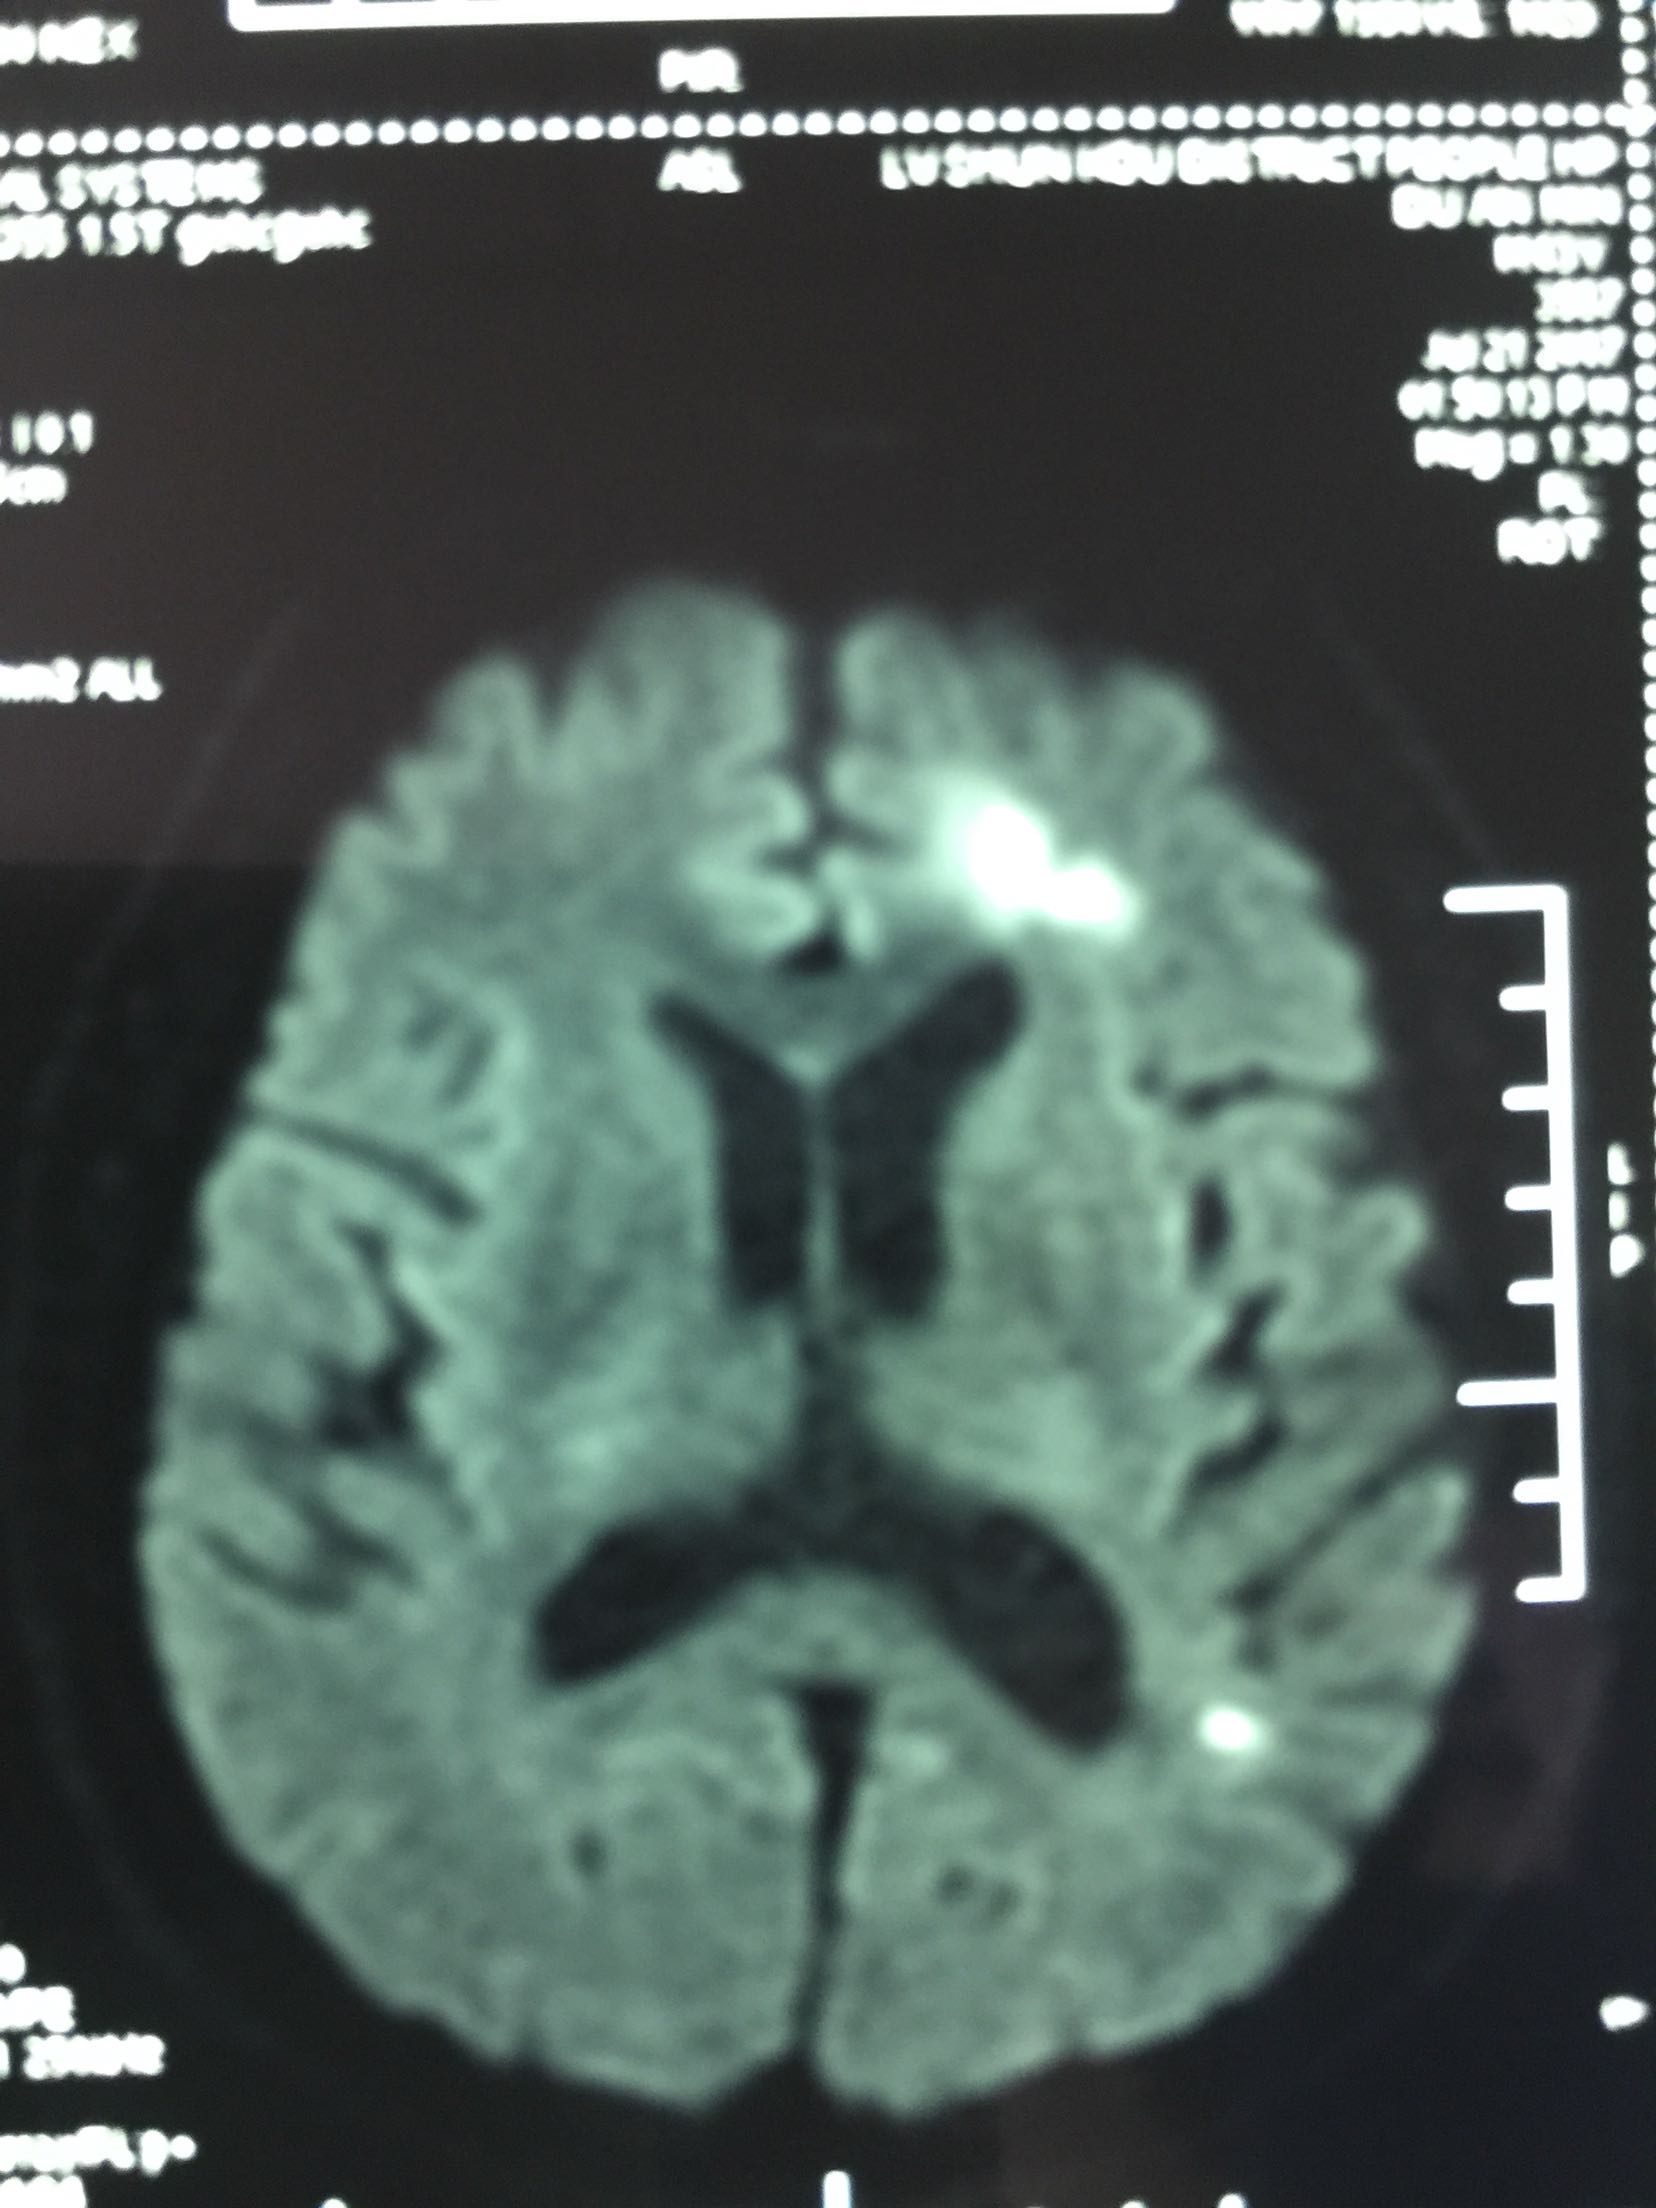

查体:T:36.5℃ P:68次/分 R:18次/分 Bp:120/70mmHg 内科系统:正常 神经系统:神志清楚,言语欠流利,查体合作,平车推人病房。左侧鼻唇沟浅,伸舌左偏,左侧肢体肌力0级,左侧肢体腱反射消失,左巴士征阳性。 辅助检查:血尿常规:正常 肝功、生化:正常 LDL-ch:5.12mmoL/l 心电图:窦性心律 头MRI+MRA、头CTA:

见下图